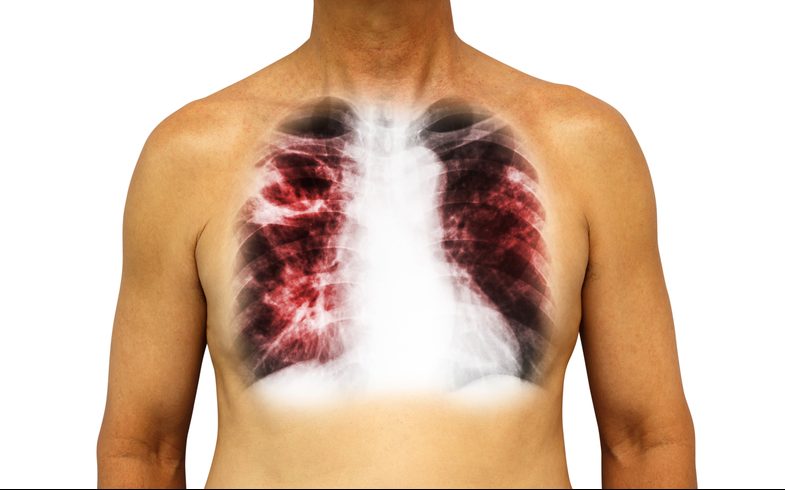

Коллапсотерапия – один из популярных и широко применяемых методов лечения туберкулеза легких в мире. Его эффективность давно доказана большим количеством положительных результатов у пациентов туберкулезных диспансеров.

Данный метод основан на уменьшении объема пораженного легкого при помощи преднамеренного введения воздуха специальным аппаратом в плевральную или брюшную полость с лечебной целью.

Искусственным пневмотораксом называется введение воздуха в плевральную полость для создания коллапса (спадения) пораженного туберкулезом легкого. До открытия специализированных химиопрепаратов против туберкулеза данный метод считался одним из самых эффективных в лечении больных.

Уменьшение объема пораженного легкого и его компрессия вызывает спадение каверн и других очагов поражения, ускоряются процессы регенерации ткани за счет создания относительного покоя легкого. Происходит более скорое заживление и задерживается поступление токсических веществ из пораженных туберкулезом очагов в здоровые ткани, что способствует значительному снижению общей интоксикации организма.